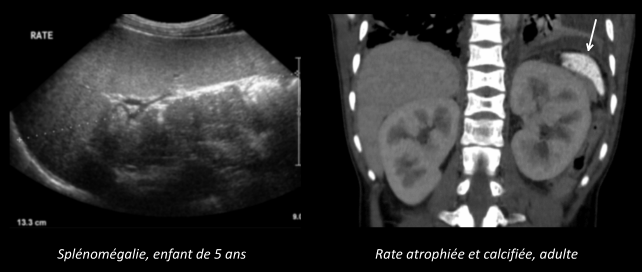

Rate

- Infarctus à répétition → Asplénie fonctionelle

- Splénomégalies

- Rates atrophiques et calcifiées (à long terme) = auto-splénectomie

- Syndrome de Séquestration splénique = Splénomégalie qui séquestre +++ le volume sanguin = Choc hypovolémique !